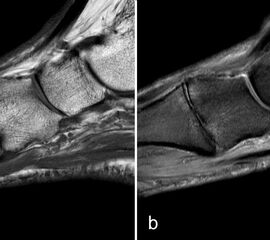

Zwischen der plantaren Platte und der Grundphalanx ist in der Mittellinie des Gelenkes ein kleiner Rezessus vorhanden (Abb. 9).

Dieser flüssigkeitsgefüllte Raum darf nicht als Ruptur der plantaren Platte fehlinterpretiert werden 23. Verletzungen der plantaren Platte erfassen immer auch den medialen oder lateralen Zügel.